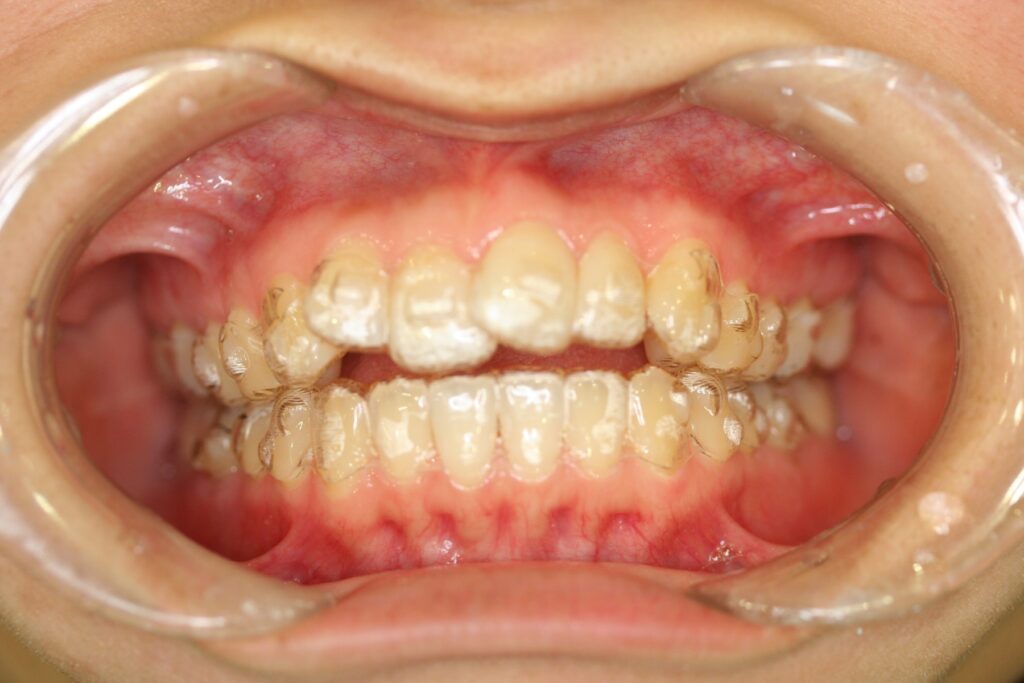

治療実績(症例) アライナー矯正 症例1 上顎前突症例 症例2 上下顎前突症例 症例3 叢生 症例4 開咬 症例5 開咬(外科的矯正治療) アライナー矯正 Post Share Hatena Line RSS feedly Pin it note 1.主訴2.診断名3.初診時年齢4.治療に用いた主な装置とオプション5.抜歯部位6.治療期間・通院回数7.総額と費用内訳総額相談検査・診断料調整料4,000円8.リスク・副作用 治療前 治療中 治療後